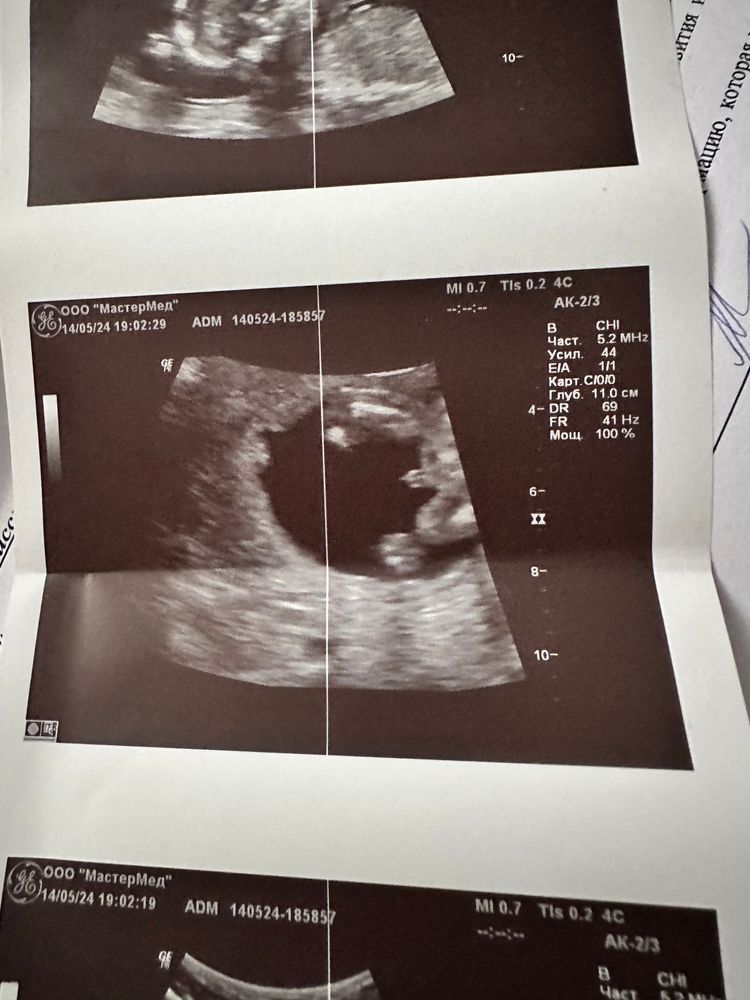

Natali Kitten в Благополучная беременность 2 года Мальчик или девочка Анализы, скрининги Пол ребенка? Посмотрите еще 20 записей на эту тему Лучший ответ Вероника Ну очевидно же 14.05.2024 Ответить Отменить Ответить Света Светлая Мальчик) 14.05.2024 Ответить ИЛИОНА Диагностик Экстрасенс Мальчик 14.05.2024 Ответить Буду мамой дочки Мальчишка 💙 14.05.2024 Ответить Вероника Мальчик 14.05.2024 Ответить Валентина Похож на мальчика) 14.05.2024 Ответить Екатерина Мальчик 14.05.2024 Ответить наташа Я думаю мальчик) 14.05.2024 Ответить Нюша Пипунька на фото, вроде же мальчик 14.05.2024 Ответить Я Мальчик 14.05.2024 Ответить Низкий гемоглобин Проблемы с почками при беременности Чаты Беременных Выберите чат: Январята-2026 Февралята-2026 Мартята-2026 Апрелята-2026 Майчата-2026 Июнята-2026 Июлята-2026 Августята-2026